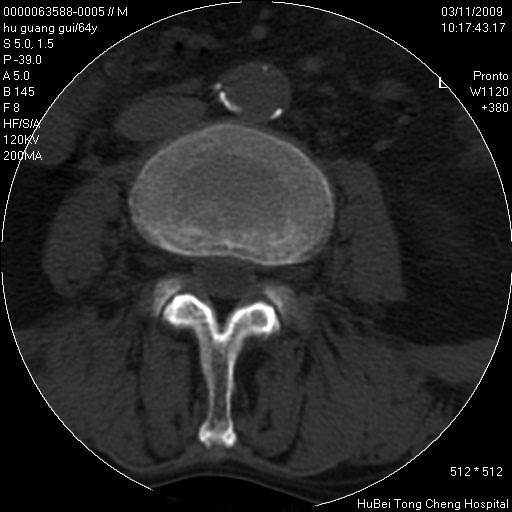

患者 男,64岁。腰痛十余天。(临床未提供其他病史)

临床诊断:腰痛原因待查(腰椎间盘突出症?)。

腰椎间盘ct轴位平扫(层厚5mm,层距4mm),图像如下:

腰椎退行性变,腰4—5椎间盘膨出。

1.腰椎退行性变,腰4—5椎间盘膨出。

1)腰椎退行性变,l4—5椎间盘膨出。2)骶骨右侧块骨转移瘤可能,3)水平骶椎。建议作一步检查。